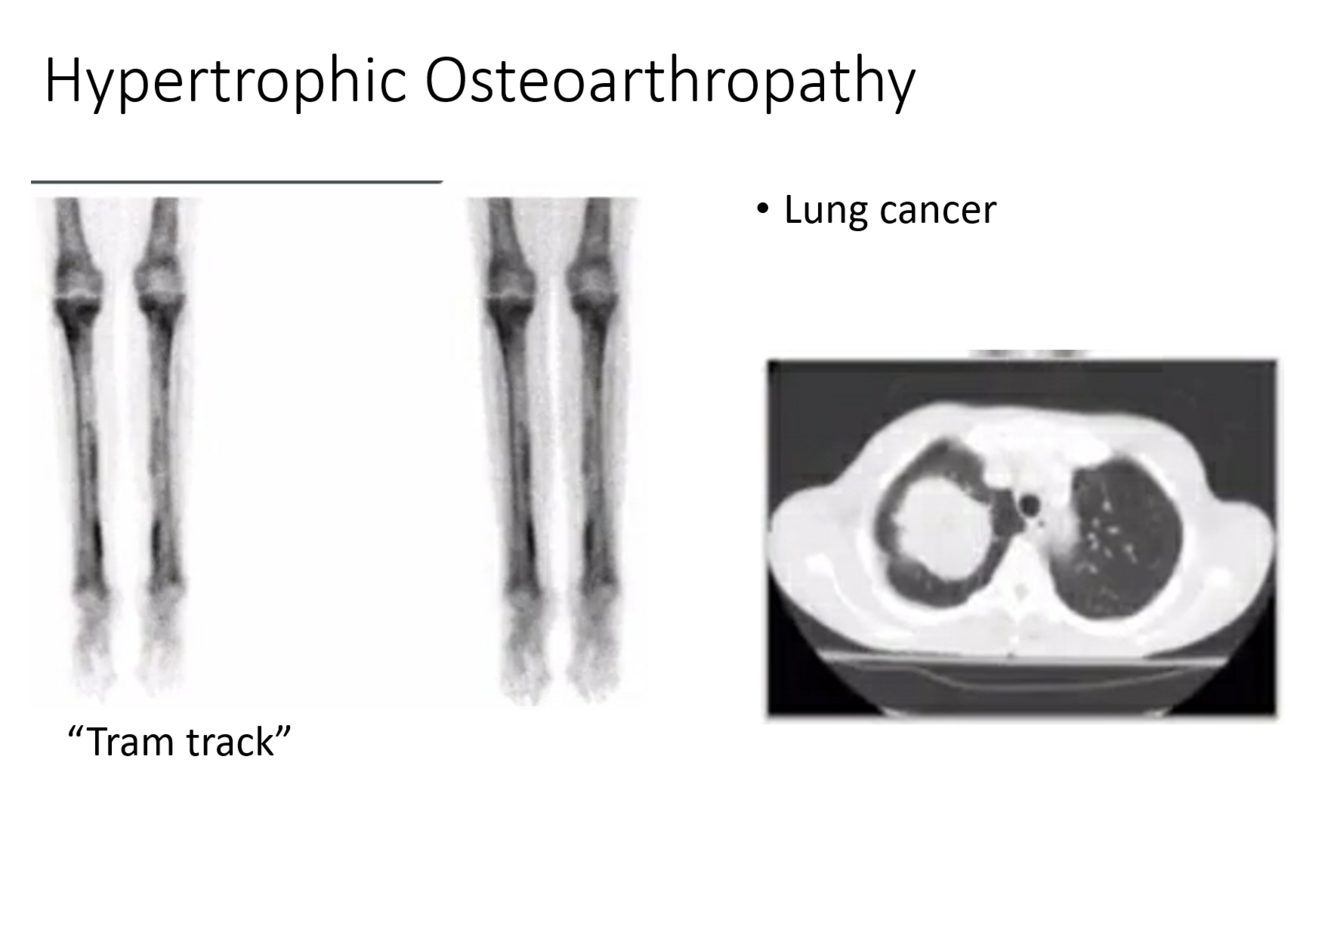

What additional imaging do you want?

CT Chest